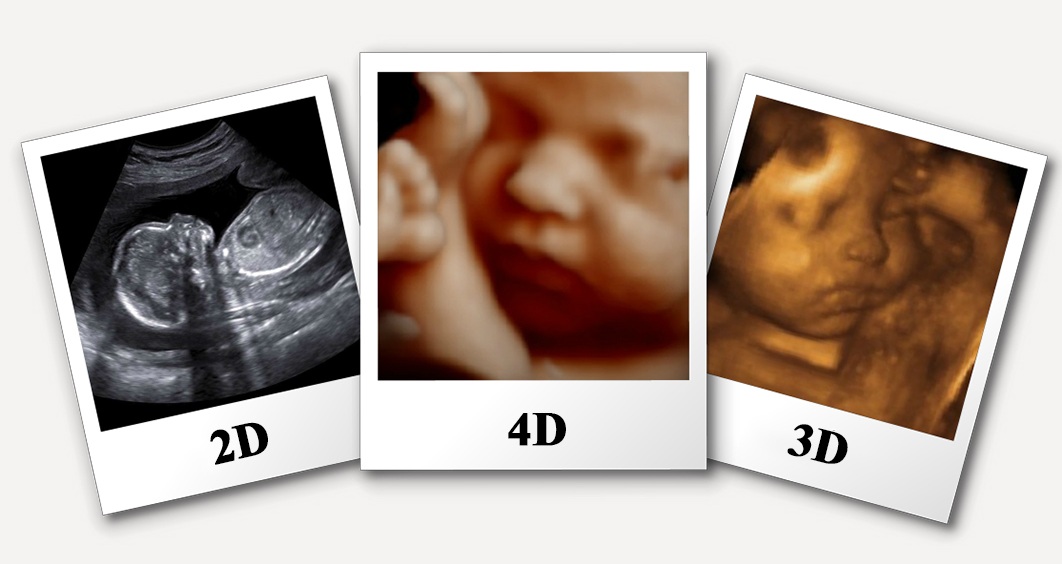

$80.00 USDThe primary goal of 4D Ultrasound is to provide highly detailed, dynamic images, offering greater diagnostic clarity and a unique interactive experience, particularly for expectant parents. This technology enhances the assessment of fetal development, maternal health, and various internal organ structures with superior spatial and temporal resolution.

The 4D Ultrasound procedure is a comfortable, non-invasive process. The patient will be asked to lie comfortably on an examination table, typically on their back. A clear, water-based, hypoallergenic gel is applied to the skin over the area of the body to be scanned (e.g., the abdomen for prenatal scans, the pelvic region for gynecological examinations, or specific organ areas). The sonographer, a highly trained technologist, then gently moves a handheld device called a transducer over the gelled skin. This transducer emits high-frequency sound waves that travel into the body and bounce off internal structures, creating echoes. These echoes are captured by the transducer and instantaneously transmitted to a sophisticated computer system, which processes them into live, moving three-dimensional images displayed on a monitor. The sonographer will carefully capture various views and take necessary measurements. Patients may often be able to observe the real-time images during the scan. The entire procedure is painless and generally lasts between 20 to 45 minutes, depending on the specific area being examined and the level of detailed visualization required.

<ul><li><strong>Enhanced Diagnostic Accuracy:</strong> Provides dynamic, three-dimensional views, offering superior detail for detecting subtle anomalies or understanding complex anatomies that might be missed in 2D scans.</li><li><strong>Real-time Visualization:</strong> Allows for immediate observation of movements, blood flow, and organ function, which is crucial for dynamic assessments, particularly in fetal studies and cardiac evaluations.</li><li><strong>Non-invasive and Safe:</strong> Utilizes high-frequency sound waves rather than ionizing radiation, making it completely safe for all patient populations, including pregnant women and fetuses, with no known harmful side effects.</li><li><strong>Improved Patient Experience & Bonding:</strong> Offers a profound emotional experience for expectant parents, allowing them to see their baby's live movements and expressions, fostering an early connection.</li><li><strong>Better Pre-Procedural Planning:</strong> More detailed and dynamic pre-procedure imaging can aid specialists in planning subsequent interventions or treatments if required, leading to better outcomes.</li><li><strong>Cost-Effective Advanced Imaging:</strong> Especially in destinations facilitated by DivinHeal like India, 4D Ultrasound offers high-definition, state-of-the-art imaging at a fraction of the cost found in many Western countries, without compromising quality.</li></ul>